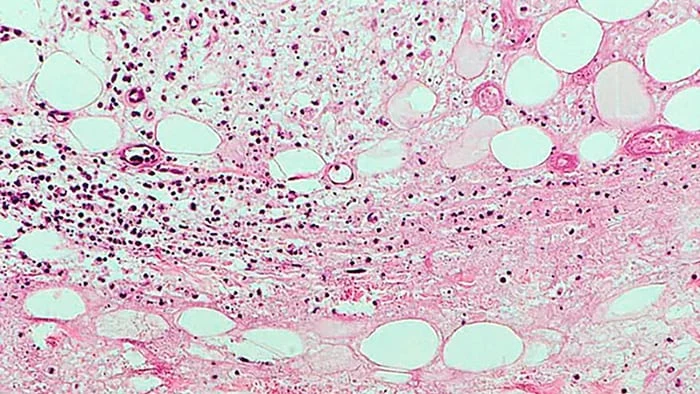

Loét Buruli đang khiến các nhà nghiên cứu đau đầu. Ảnh: Guardian

Dấu hiệu đầu tiên của căn bệnh là một vết sưng không đau trên da thường bị nhầm là vết côn trùng cắn. Tuy nhiên, vài tháng sau, những vết loét trông như “miệng núi lửa” sẽ xuất hiện và lan rộng. Người bệnh cảm thấy vô cùng đau đớn khi vi khuẩn xâm nhập, gặm nhấm qua da, mao mạch, phá hủy hệ miễn dịch và dẫn đến hoại tử, tổn thương xương. Nếu không được điều trị kịp thời , một số trường hợp buộc phải cắt bỏ chi.